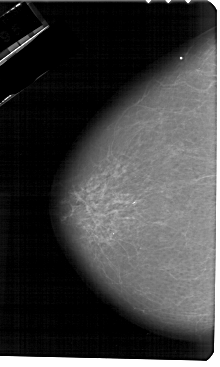

A_1267_1.RIGHT_MLO

RIGHT_MLO LINES 5491 PIXELS_PER_LINE 3121 BITS_PER_PIXEL 12 RESOLUTION 43.5 OVERLAY